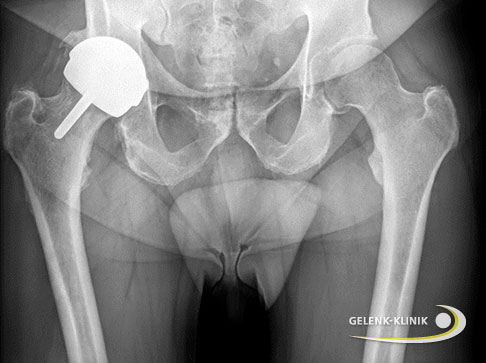

Teilprothese für junge Erwachsene mit Hüftdysplasie: Hüftüberkronung für hohe Lebensqualität

Eine bestehende Restdysplasie eines oder beider Hüftgelenke macht sich nicht erst im fortgeschrittenen Lebensalter bemerkbar. Manche Patienten, die sich in der Gelenk-Klinik wegen starker Hüftschmerzen und eingeschränktem Bewegungsradius vorstellen, haben gerade erst ihr 20. Lebensjahr vollendet. Diese Gruppe junger Patienten stellt völlig andere Anforderungen an ein Hüftimplantat als die ältere Generation:

- Eine Prothese muss den alltäglichen und sportlichen Aktivitäten lange Stand halten.

- Wegen der hohen Aktivität der Patienten sollte der Gelenkersatz aus abriebfesten Materialien bestehen.

- Die Implantation wie auch der Ersatz (Revision) der Prothese sollte möglichst knochensparend und schonend erfolgen.

Diesen Ansprüchen gegenüber stehen die hohe Knochendichte und eine gute gesundheitliche Konstitution der jungen Patienten, die den Einsatz einer Oberflächenersatzprothese nach McMinn in den Fokus rücken. Bei diesem auch Hüftkappe oder Hüftkrone genannten Gelenkersatz wird lediglich die geschädigte Gelenkfläche des Oberschenkelkopfes ersetzt ‒ ähnlich wie wir es von einer Zahnkrone kennen. Sowohl der Oberschenkelkopf als auch der Knochenschaft bleiben bei Einsatz einer McMinn-Prothese erhalten. Die Hüftkrone besteht aus einer Kobalt-Chrom-Verbindung mit sehr guten Langzeitergebnissen bezüglich Stabilität und Verträglichkeit.

Patienten mit McMinn-Prothese steht hinsichtlich ihren sportlichen Aktivitäten nichts im Weg ‒ außer der eigenen körperlichen Konstitution. Es existieren kaum Einschränkungen in der Hüftbeweglichkeit, sogar Reitsport kann wieder ohne Schmerzen ausgeübt werden.